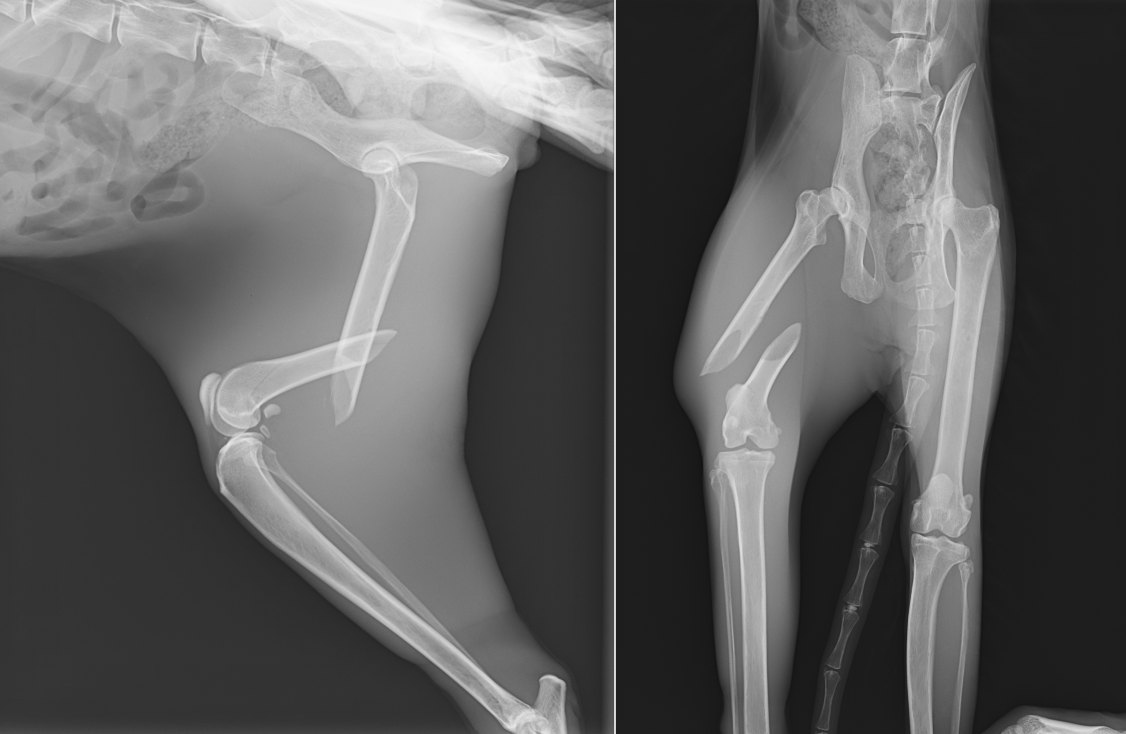

老齢猫の大腿骨骨幹部中央の斜骨折です。老齢猫では骨が固く、もろくなっていくので簡単に骨が割れていくことがあります。

なるべくそうならないよう髄内ピンを設置してからプレート設置を行いましたが、それでも数箇所割れてしまったところがあります。SOPプレートというロッキングプレートの一種で固定しています。老齢のため、骨化を促進するためフリーズドライのパウダーを入れています(写真右)

術後レントゲンです。アライメント(向きや配置)も問題なく固定されています。術後すぐに歩きだし、3週後には走り回って、家を脱走するくらいとのことでした。